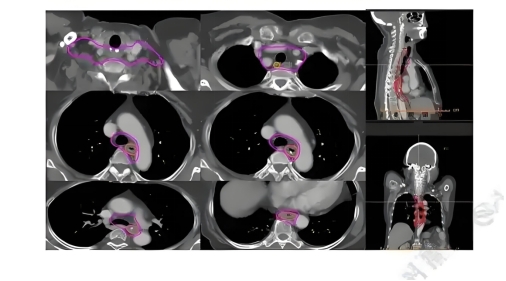

五、治疗全流程:科学规划保障疗效

放疗不是一蹴而就,分阶段管理是关键。整个过程分三步走:

阶段1:定位与计划(1~3天)